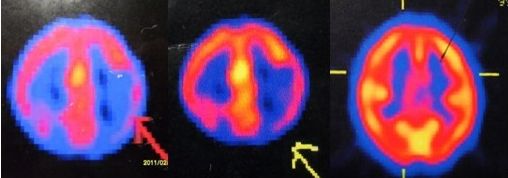

附图:癫痫异常灌注灶中药组修复过程的SPECT显像变化

例1示:A治疗前L顶颞低灌注 B 治疗后第12月低灌注改善 C第48月ECT正常

儿童癫痫,WX,女,8岁,全身强直阵挛发作。病程8月,抗痫药+天麻治疗,三次SPECT显像变化,局灶低灌注变小至修复正常。6年无发作,6次V-EEG后4次正常,停药1年。